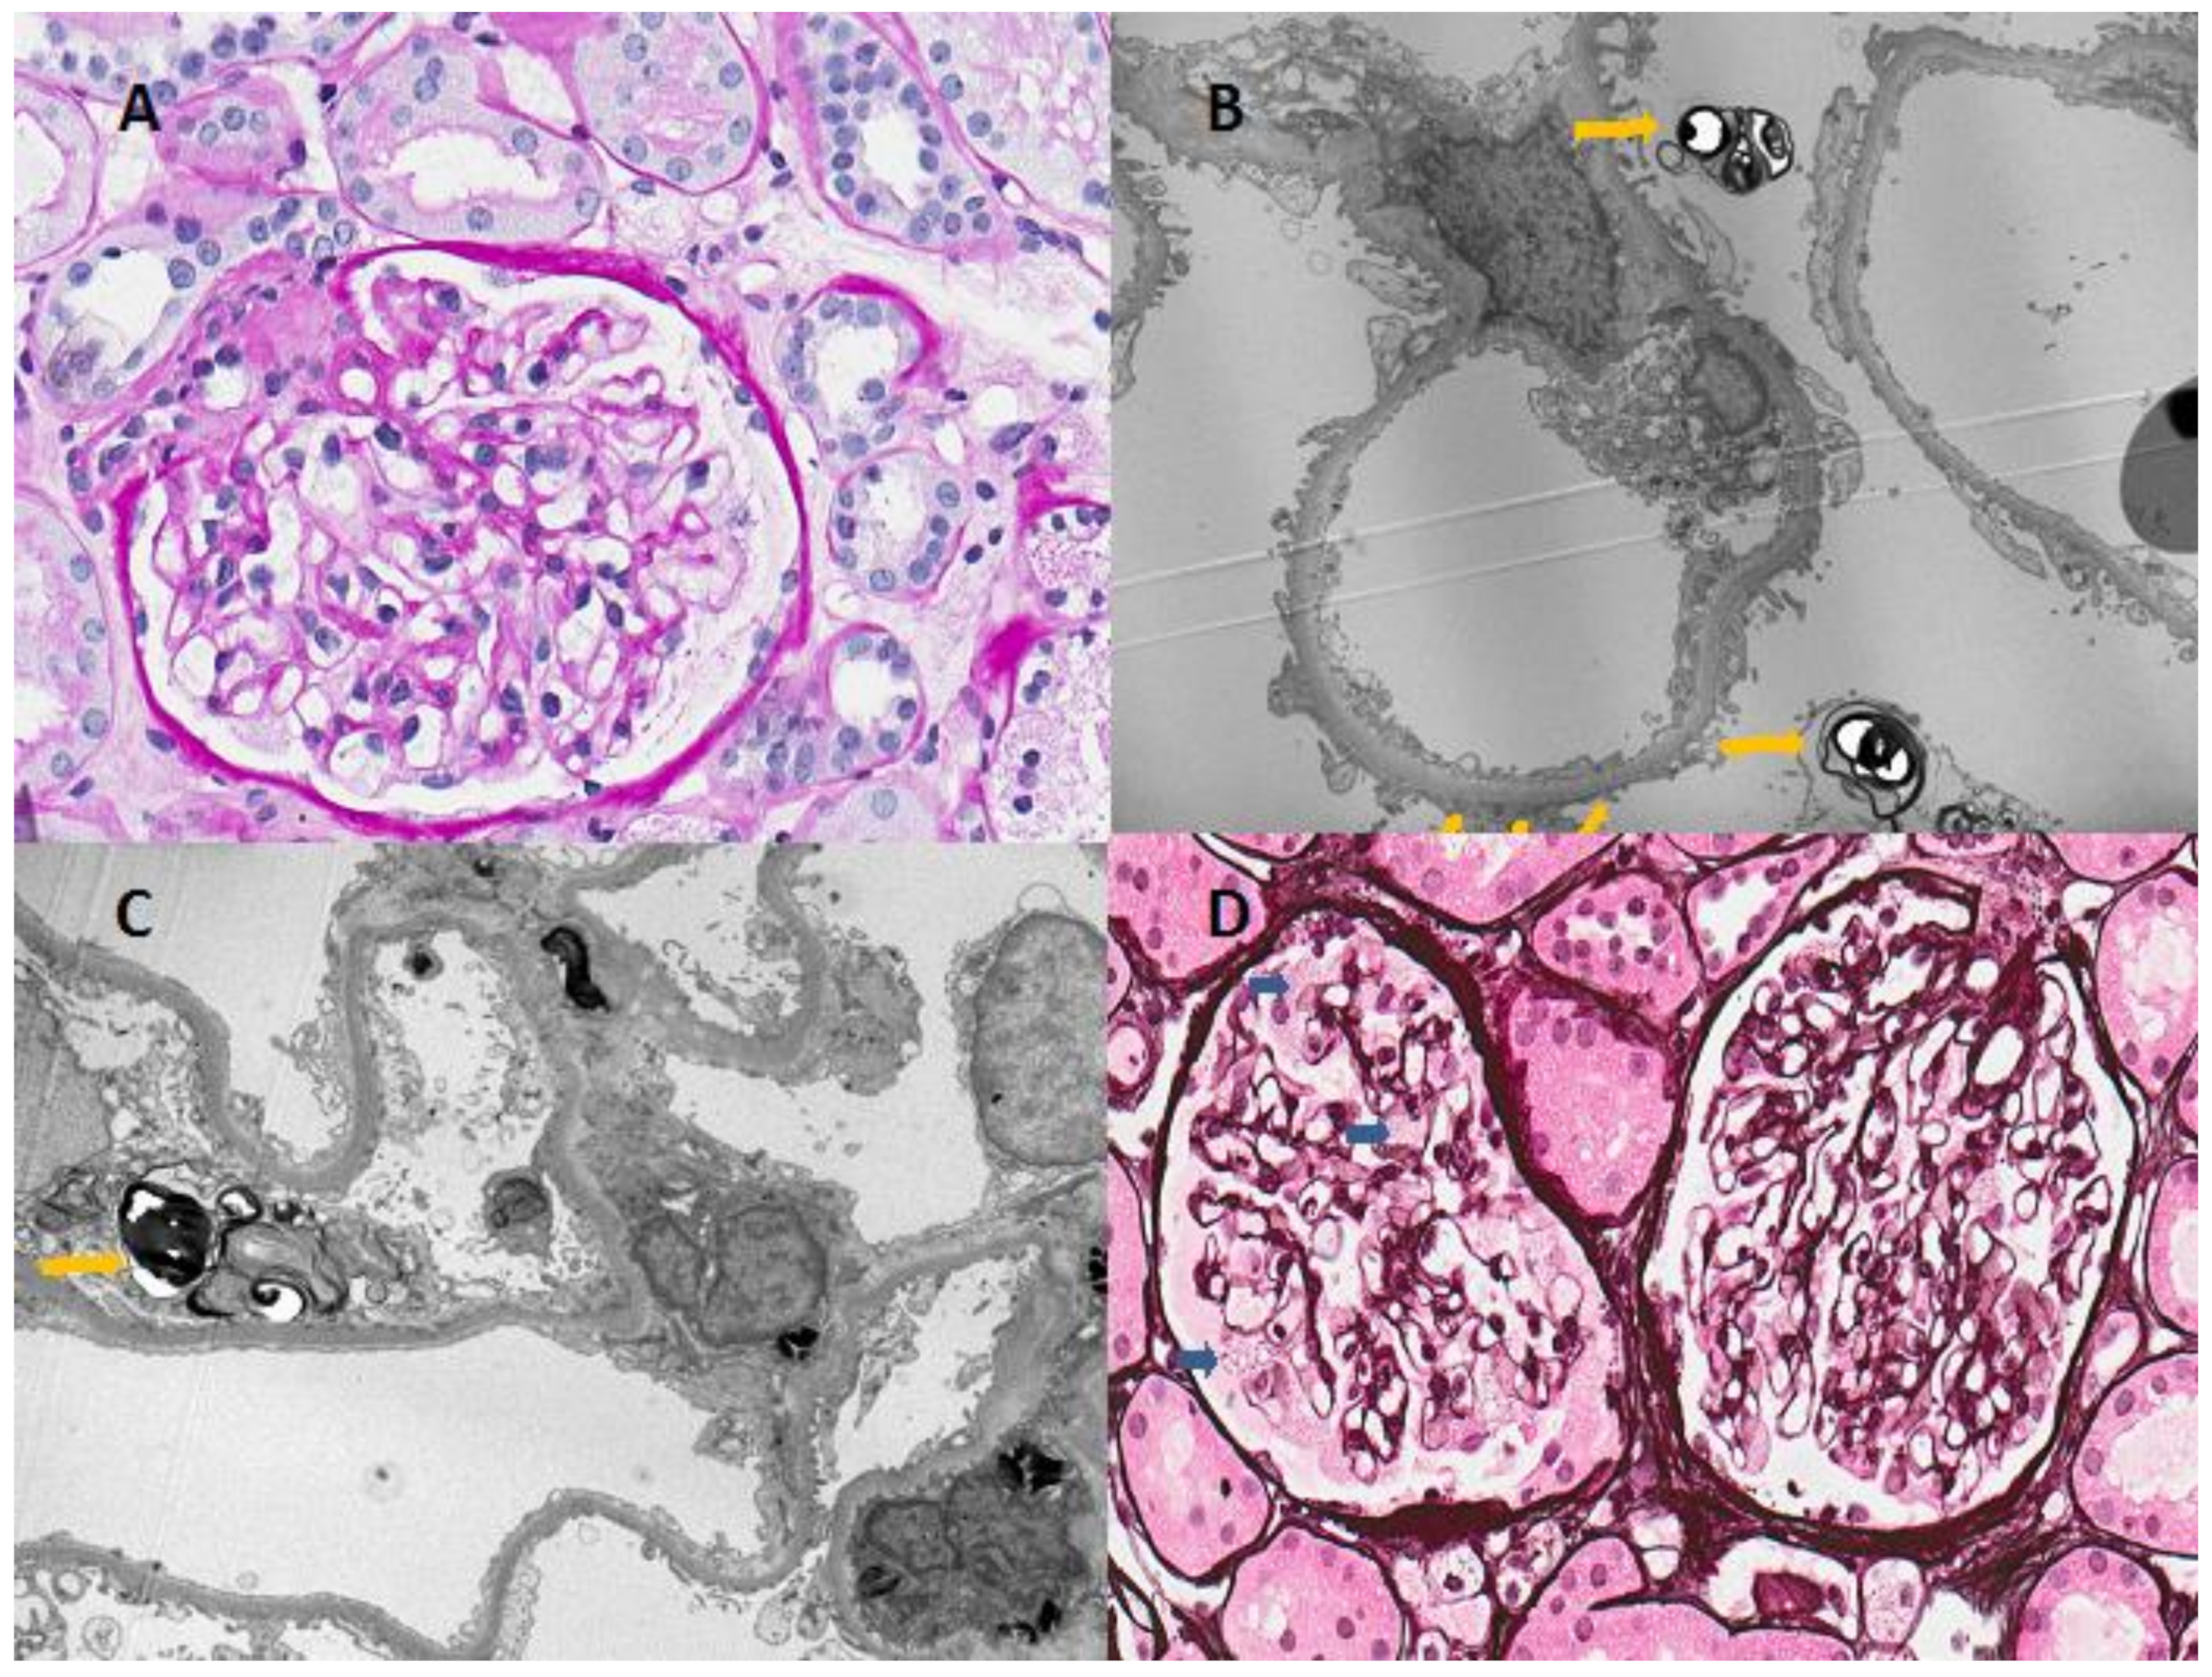

Since a previously unreported mutation was detected, a kidney biopsy was performed on the proband to support the diagnosis, in which ultrastructural pathognomic changes consistent with Fabry disease were found (Figure 2). Light microscopy examination showed enlarged podocytes with foamy vacuoles. Electron microscopy identified typical electron-dense multilamellar inclusions and zebra bodies in the cytoplasm of podocytes as well as focal podocyte foot process effacement.

Figure 2.

Light and electron microscopic findings of renal biopsy from the patient. (A) Microscopic examination revealed minimal mesangial proliferative changes; (B,C) Typical findings of Fabry disease-multilamellated myelin figures (yellow arrowhead) are seen in the cytoplasm of podocytes on electron microscopy; (D) Light microscopy showed the vacuolization of podocytes (blue arrowhead), although the patient had normal renal function and nonsignificant proteinuria (Haemotoxylin and Eosin stain, ×400).